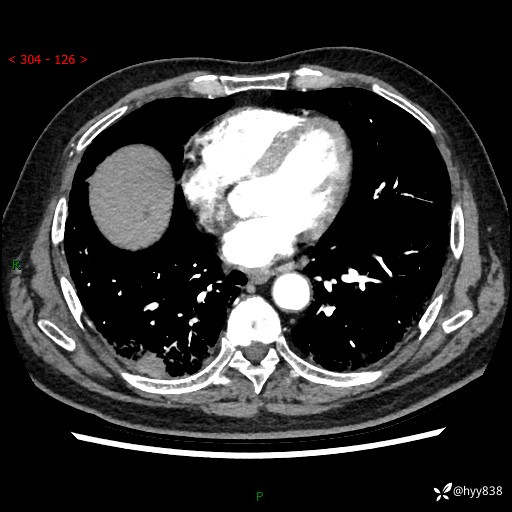

71岁/男,咳嗽伴气促半月。一年前肺手术史,又见两个结节,穿刺结果意外---结果公布~

【患者信息】:71岁/男

【主诉】:咳嗽、咳痰伴气促半月

【现病史】:患者半月前无明显诱因出现咳嗽、咳痰,为白色粘痰,无明显加重与缓解因素,伴气促,无发热,无大量脓痰,无胸痛、咯血,无哮鸣音,到我院就诊,胸部CT示右肺结节增大,并口服药物治疗无明显好转,具体用药不详,为求进一步治疗随来我院,经门诊以“孤立性肺结节”收入我科。 病程中患者精神、饮食可,睡眠不佳,大小便正常,体力下降,体重未见明显下降。

[既往史]:2022-06于当地第一人民医院确诊慢阻肺,现规律使用杰润(1次/日);2023-04-06于当地市第一人民医院行胸腔镜右肺上叶楔形切除术+右肺上叶切除术+淋巴结清扫术+胸膜黏连松解术,确诊为右肺鳞癌 pT2aN0M0 Ib期

【检查】:胸部CT平扫+增强